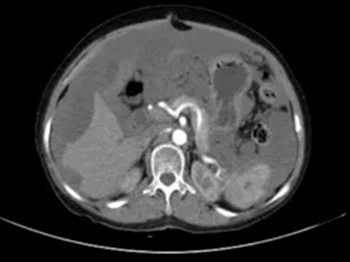

另一位80岁老年女性患者因精神萎靡、低热就诊,腹部CT检查发现其腹腔积液分布颇具特征:肝脏边缘呈“扇贝形”受压,大网膜增厚呈“饼状”。外院治疗效果不佳,遂至郑大五附院求诊。

杨战锋主任详细询问病史并全面查体后,初步判断为腹腔粘液瘤可能。排除手术禁忌后,行腹腔镜探查,术中见腹腔、盆腔内大量胶冻样粘液性腹水,阑尾可见实体肿瘤,子宫及双侧附件亦见粘液样肿块。

遂联合妇科专家共同手术,术后病理证实为阑尾低级别粘液性肿瘤。 谜底就此揭开:这是一种较为罕见的腹膜假黏液瘤。阑尾的黏液瘤细胞在腹腔内悄然播散,持续产生大量胶冻状黏液,逐渐形成特征性的“黏液性腹水”。这类积液既非普通的漏出液,也非化脓性渗出液,而是一种需要外科肿瘤减灭术等综合治疗的肿瘤性疾病。